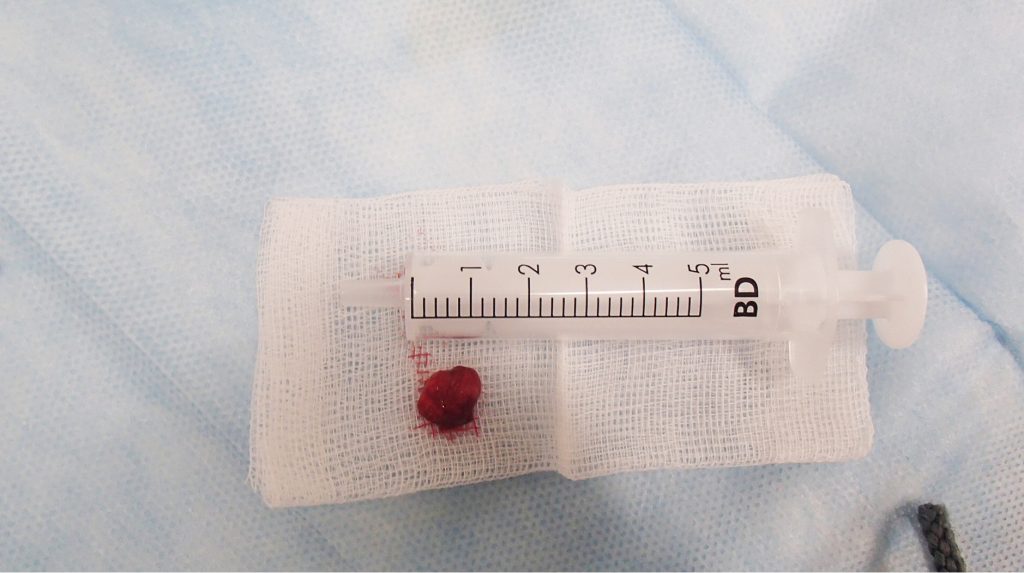

Streszczenie: Przewlekłe zapalenie tkanek około-wierzchołkowych jest to proces zapalny wywołany przez przetrwałą infekcję bakteryjną w systemie kanałów korzeniowych, która prowadzi do destrukcji więzadeł ozębnej, resorpcji kości i powstania tkanki ziarninowej. Celem artykułu jest porównanie metod leczenia niechirurgicznego i chirurgicznego pacjentów z rozległymi zmianami okołowierzchołkowymi w obrębie zębów siecznych dolnych.

Summary: Chronic apical periodontitis is inflammation caused by persistent bacterial infection of the root canal system, which leads to the destruction of the periodontal ligament, bone resorption and formation of granulation tissue. The aim of the article is to compare the methods of nonsurgical and surgical treatment of large lesion in periapical area of the lower incisors.

Zapalenie tkanek okołowierzchołkowych jest jedną z najczęstszych patologii w obrębie wyrostków zębodołowych szczęk i części zębodołowej żuchwy [1]. W postaci przewlekłej wywoływane jest przez przetrwałą infekcję bakteryjną w systemie kanałów korzeniowych [2, 3].